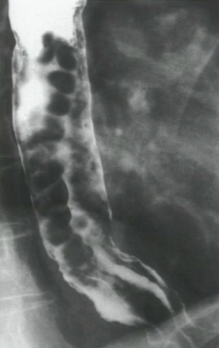

What is your diagnosis in this patient with liver disease?

Uphill varices. Note the serpigineous nodularity in the distal esophagus. This is a result of portal hypertension